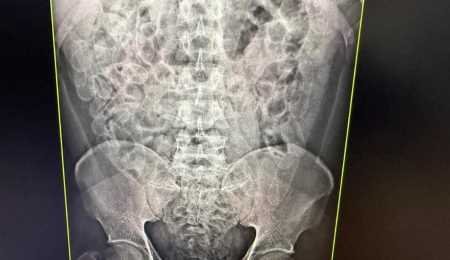

Raio-x de um dos passageiros que engoliram cápsulas de drogaCom o apoio de um cão de faro da Receita Federal, dois passageiros bolivianos, de 24 e 31 anos, foram detidos por tráfico de drogas. Levados à Santa Casa, exames de raio-x confirmaram que ambos haviam ingerido cerca de 100 cápsulas de cocaína, totalizando 2,2 quilos da droga. Após a expulsão do entorpecente, os suspeitos foram encaminhados à Polícia Federal.